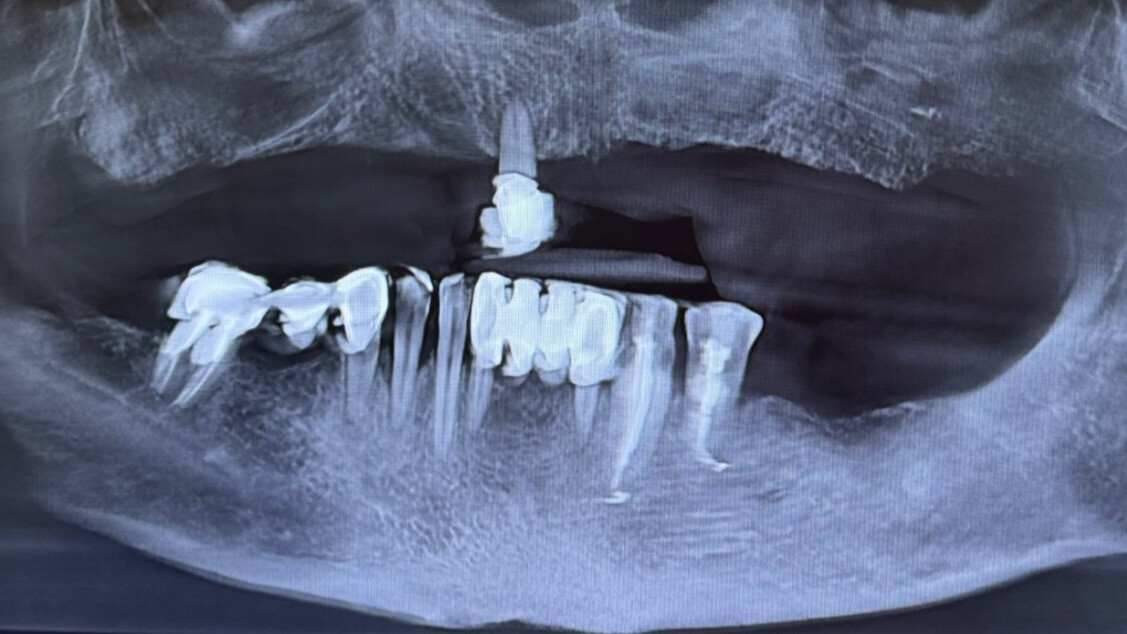

Імплантація зубів All-on-6, Все-на-шести

Вихідна ситуація: скарги пацієнта на повну відсутність зубів на верхній щелепі та часткову втрату на нижній. Це призводило до труднощів у жуванні, порушення дикції та зниження якості життя. Після детального обстеження та консультації було прийнято рішення провести протезування за методикою "все на шість" на верхній щелепі. Ця технологія передбачає встановлення шести імплантатів, на яких фіксується незнімний протез. Це дозволяє відновити повну функціональність та естетику зубного ряду. На цей час пацієнт перебуває на етапі підготовки до імплантації. Метою є не тільки відновлення функціональності, але й покращення естетичного вигляду, що позитивно вплине на самооцінку та соціальну активність пацієнта.